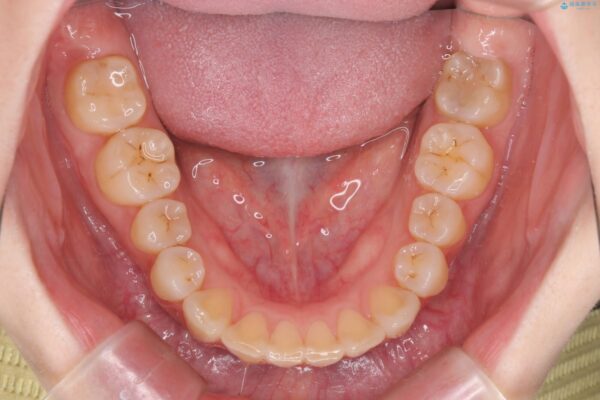

治療後

傾いた前歯、インビザラインで改善 治療後画像 傾いた前歯、インビザラインで改善 治療後画像 傾いた前歯、インビザラインで改善 治療後画像 傾いた前歯、インビザラインで改善 治療後画像